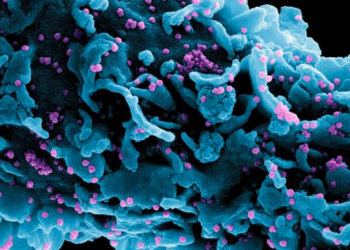

Sputnik V muestra una protección contra ómicron 2 veces superior a la de Pfizer

2022-01-20 Nuevo Mundo - 96.1 La vacuna rusa contra el coronavirus Sputnik V muestra una fuerte...

Descubren una nueva variante del coronavirus en Francia

2022-01-05 Nuevo Mundo - 96.1 Justo en el momento en que se empieza a establecer que...